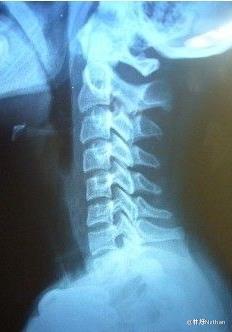

5,颈椎生理曲度变直

当长时间不正确的坐姿、或是长时间的劳累、颈椎缺少活动、脊柱损伤、脊柱钙化等就会导致颈椎生理曲度变直。

http://pic3.zhimg.com/e9c579b18b4837b2314679aa805cf082_b.jpg